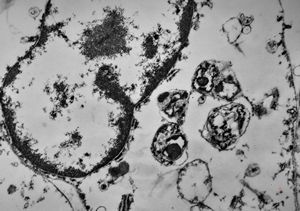

F,50y. | progressive multifocal leukoencephalopathy- viral particles in a glial cell

F,50y. | progressive multifocal leukoencephalopathy- viral particles in a glial cell

F,50y. | progressive multifocal leukoencephalopathy- viral particles in a glial cell